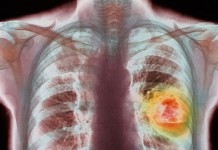

Рак легких. Наглядное руководство

Узнайте больше о самом распространенном виде рака.